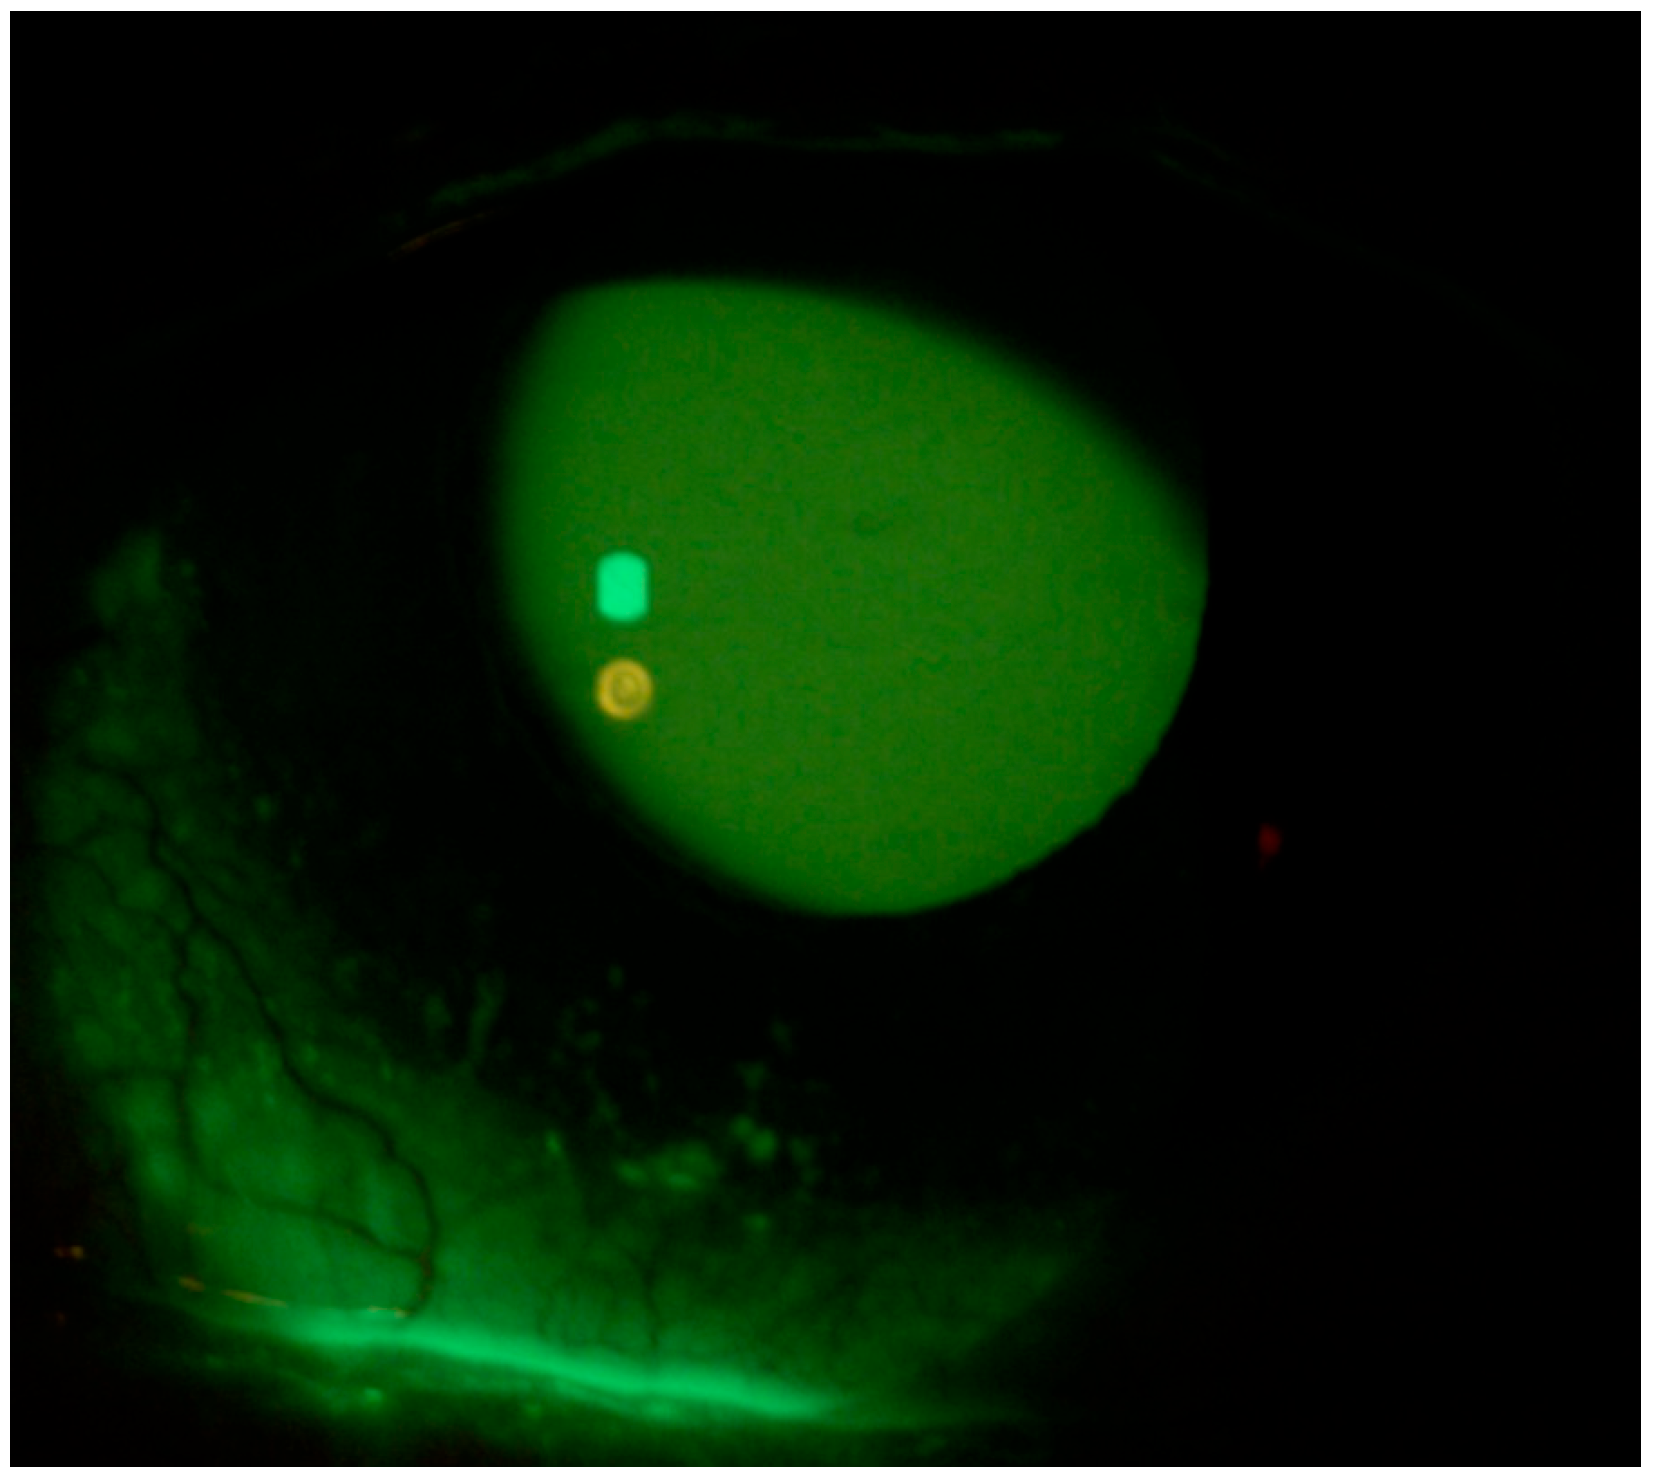

2. Case Description